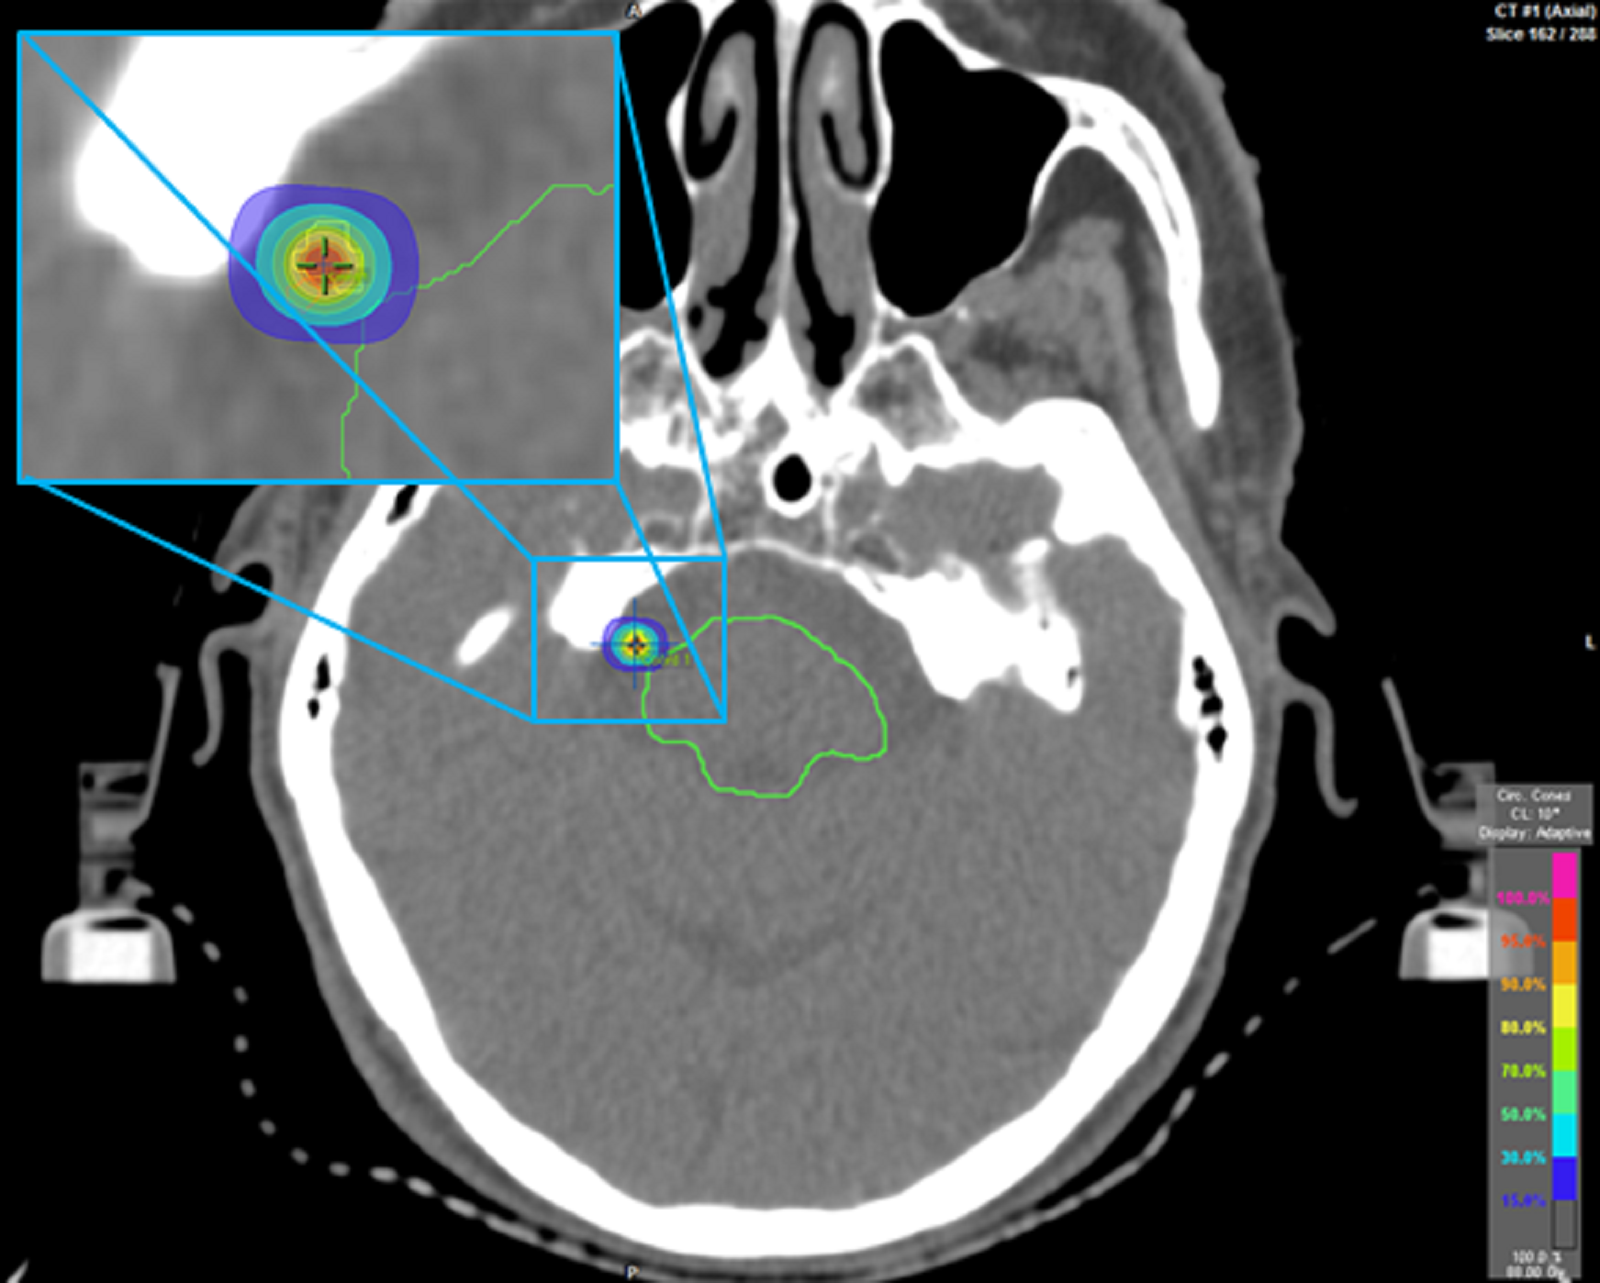

From www.cureus.com

Stereotactic Radiosurgery for Trigeminal Neuralgia Caused by Vertebrobasilar Compression A Stereotactic Radiosurgery Trigeminal Neuralgia stereotactic radiosurgery is an effective treatment option for trigeminal neuralgia (tn), with frameless. The aims of this systematic review are to provide an objective summary of the published. the purposes of this study are to assess the effectiveness of cyberknife® stereotactic radiosurgery (srs) in. stereotactic surgery uses focused radiation to damage nerve tissue (trigeminal nerve) to prevent. Stereotactic Radiosurgery Trigeminal Neuralgia.